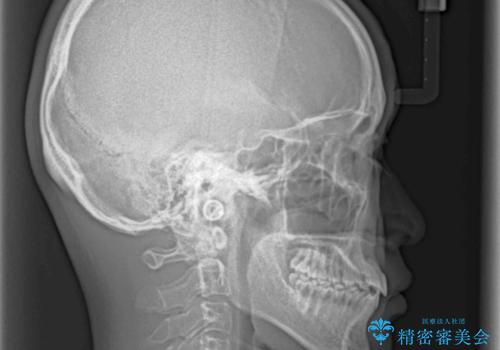

前歯のクロスバイト インビザラインによる矯正治療

奥に位置していた上の前歯が下の前歯を乗り越える際、奥歯でものを咬むことができず、辛い時期が続きました。